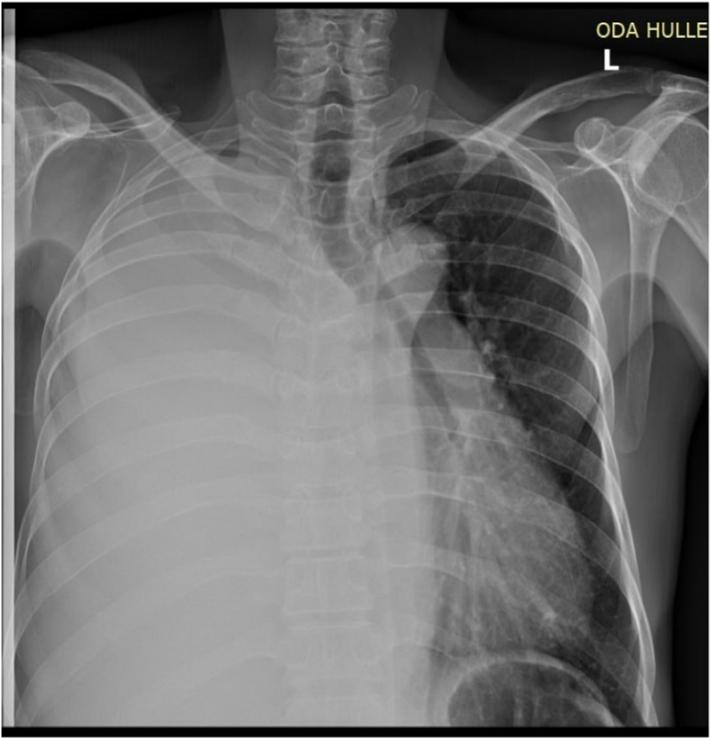

A 50 years old male patient presented to our hospital with right side chest pain and shortness of breath of 3-week duration. He had completed treatment of pulmonary tuberculosis 6 months ago. The patient was apparently healthy for the last six months after the treatment. The patient was acutely sick looking and has tachycardia with pulse rate of 115, respiratory rate was 36 and arterial oxygen saturation of 80 % with atmospheric air but becomes 96 % with facemask humidified oxygen. Tube thoracostomy and chest wall debridement was done for empyema necessitans with chest wall necrotizing fasciitis.

一名50岁男性患者因右侧胸痛和气短3周前来我院就诊。他6个月前完成了肺结核治疗。治疗后的最后6个月里,患者看起来明显健康。患者病容憔悴,心率过速,脉搏率为115次/分,呼吸频率为36次/分,在空气中动脉血氧饱和度为80%,但使用面罩湿化氧气时升至96%。对患有胸壁坏死性筋膜炎的脓胸穿破胸壁患者进行了胸腔闭式引流术和胸壁清创术。